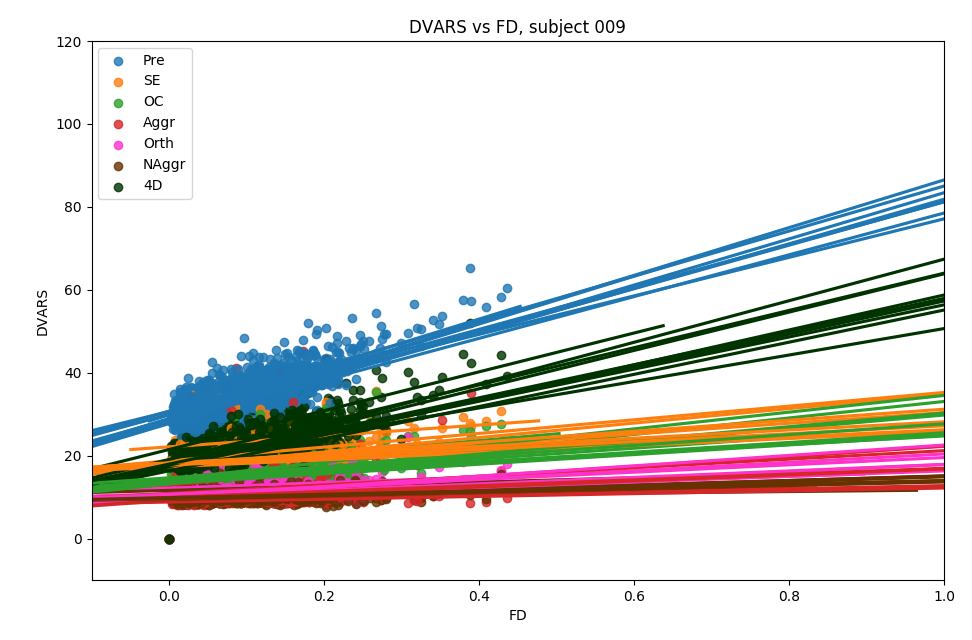

Methods: ME-ICA based denoise

- their effect in terms of making signal (DVARS) independent of motion (FD) [LME]: $$DVARS_t = \sqrt{\lang [I_t(x) - I_{t-1}(x)]^2}$$ $$FD_t=|\Delta d_x|+|\Delta d_y|+|\Delta d_z|+|\Delta \alpha |+|\Delta \beta|+|\Delta \gamma |$$

$$DVARS\sim FD\ast model+(1|subject)+(1|session)$$

- the resulting CVR and lag maps spatially [LME]: $$X\sim model+(1|subject)+(1|session)$$

- the resulting CVR and lag maps' reliability [ICC]: $$X \sim (1|subject)+(1|session)$$

We compared:

Effect of denoising approach is significant for slope (F(5,354)=177.6, p<0.001) and intercept (F(5,354)=225.7, p<0.001) of the linear regression model

DVARS vs FD

Group level, DVARS vs FD

Slope

Intercept

↓

↓

Results: motion removal

Moia et al. 2021 (NeuroImage)

\( \cdot \) timepoint \( - \) session